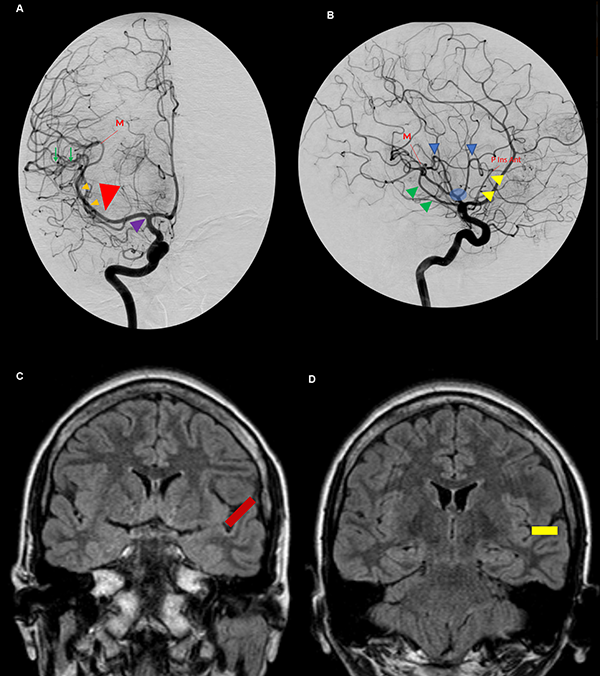

Figura 11: A. Vista anteroposterior de una angiografía carotídea derecha. El uncus (cabeza de flecha violeta) se relaciona anteriormente con el segmento proximal de M1. El ápex uncal apunta hacia la bifurcación carotídea. Inmediatamente distal al genu de la ACM se ubica la pars triangularis (cabeza de flecha roja grande). Las pequeñas cabezas de flecha naranjas indican el segmento M2 de la ACM y, consecuentemente, la corteza insular. El punto M se define como el punto donde el ramo más posterior de M2 cambia de sentido alejándose de la ínsula hacia el opérculo, en relación estrecha con el extremo posteromedial del giro de Heschl. La ínsula se proyecta desde el genu de la ACM hasta el punto M. Las ramas de M3 sobre el plano temporal tienen un curso recto (flechas verdes). B. Vista lateral de la misma angiografía. Se identifica el triángulo silviano. Su borde anterior (cabeza de flecha amarillo) y superior (cabezas de flecha azul) lo marcan los loops de M2. Su borde inferior lo indica el tronco inferior de M2 cursando por el surco limitante inferior insular (cabeza de flecha verde). Los troncos postbifurcación se ramifican cerca del polo insular y el ápex (círculo celeste). C y D. Vistas coronales de una RMN. El plano polar tiene una dirección oblicua inferior (barra roja) (C) y el plano temporal una dirección recta (barra amarilla) (D). P Ins Ant: punto insular anterior.

Anatomía vascular y su correlación angiográfica

Existe un consenso a lo largo de la literatura de que la bifurcación silviana se localiza más frecuentemente en el limen insular. Según Rhoton,12 Gibo3 y Wen,15 86-90% de las bifurcaciones se localizan proximal al o en el limen insular. Sin embargo, Türe,27 reporta en su serie que 57.5% de las ACM se bifurcan en el limen, 15% 5 a 8 mm proximal al, y 27.5% 4 a 10 mm distal al limen insular. Finalmente, Yasargil17 considera que en el 50% de los casos, M1 se divide en el limen insular. En nuestra serie, en el 50% de los casos la bifurcación de la ACM se localizó proximal al, 30% en, y 20% distal al limen insular. Así también, la presencia de ramas corticales tempranas en el 90% de nuestros especímenes, se correlaciona con el 91% publicado por Tanriover et al.26 Definimos a las ramas corticales tempranas, como aquellas arterias nacidas en M1 que no tienen relación estrecha con la corteza insular e irrigan áreas corticales temporales o frontales.

Se dice que la angiografía digital (AD) muestra el esqueleto en el cual las estructuras neurales son organizadas. Su comprensión profunda es esencial para el planeamiento quirúrgico. La corteza insular está cubierta e irrigada por el segmento M2 (Figura 7A). Consecuentemente, en una AD, el lóbulo insular se localiza inmediatamente medial a M2 (Figura 11A y B).21 Los límites anterior, superior e inferior del lóbulo insular también pueden ser reconocidos en la AD. Los puntos de cambio de dirección, o loops, de la ACM distal al genu marcan la transición M2/M3 y se localizan en el surco limitante insular anterior y superior (Figura 7A y B). El tronco inferior de M2 cursa a lo largo del surco limitante inferior (Figura 7A). El punto donde el ramo más posterior de M2 cambia de dirección y se aleja de la ínsula dirigiéndose hacia el opérculo temporal (transición M2/M3) es el punto M o silviano, en la AD (Figura 12B, 11A, 11B).12,14,15,26,30 El punto M es un reparo imagenológico de gran utilidad. Este punto indica el extremo posterior insular y la parte más posteromedial del giro de Heschl. Así también, en una incidencia anteroposterior, el punto M indica la posición de, de lateral a medial, el brazo posterior de la cápsula interna, el pulvinar del tálamo y el atrio (Figura 12B).

El triángulo silviano6,14,15 es un reparo encontrado en la incidencia lateral estricta en un AD. Sus bordes son dibujados por los loops M2 anterior y superiormente, y por el tronco inferior cursando por el surco limitante inferior insular, inferiormente. Este triángulo tiene un ángulo superoanterior recto, marcando el punto insular anterior. El contenido de este triángulo es el lóbulo insular y el core central. Inmediatamente por fuera del triángulo se encuentran los ventrículos laterales (Figura 11B).

La bifurcación carotídea se relaciona con el ápex uncal y el segmento proximal de M1 se relaciona inferiormente con el segmento anterior del uncus. Más aún, el genu de M1 se localiza en el limen insular, por lo tanto, en una AD, marca el borde anterior de la ínsula. La pars triangularis está ubicada unos milímetros distales al genu de M1. Dado que el giro precentral cubre el tercio medio de la ínsula, se puede inferir que el giro precentral en una AD se localiza en el punto medio del triángulo silviano. Finalmente, el extremo posterior del lóbulo insular se localiza en el punto M. Consecuentemente, lesiones vascularizadas localizadas en el genu de M1, son encontradas unos pocos milímetros proximales a la pars triangularis, cerca del polo insular; lesiones localizadas inmediatamente distal al genu, se relacionan superficialmente con la punta de la pars triangularis; y aquellas posicionadas en el punto medio entre el genu y el punto M, son mediales al giro precentral (Figura 11A y B).15

Las ramas M3 que cursan sobre el plano polar son más curvilíneas que aquellas del plano temporal, a causa de la superficie relativamente más plana de la primera. El primer segmento recto de M3 identifica el extremo lateral del giro de Heschl (Figura 11A).15 Entonces, el giro de Heschl está enmarcado entre el punto M y el primer tramo recto de M3 (Figura 7B).